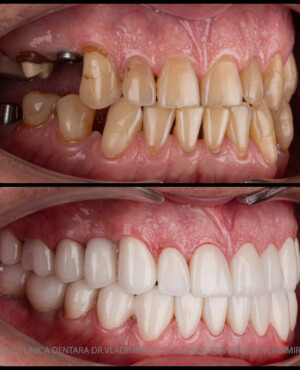

Protezarea pe implanturi dentare este soluția modernă, estetică și funcțională pentru înlocuirea dinților lipsă. Această procedură combină precizia chirurgicală cu tehnologia avansată de laborator pentru a reda pacienților zâmbetul natural, vorbirea clară și capacitatea de a mânca fără restricții.

La Clinica Dentară Dr. Grossu din Chișinău, oferim protezări pe implanturi dentare personalizate, realizate de o echipă multidisciplinară, cu ajutorul celor mai noi tehnologii digitale și materiale biocompatibile.

- Estetică superioară – imită perfect dinții naturali